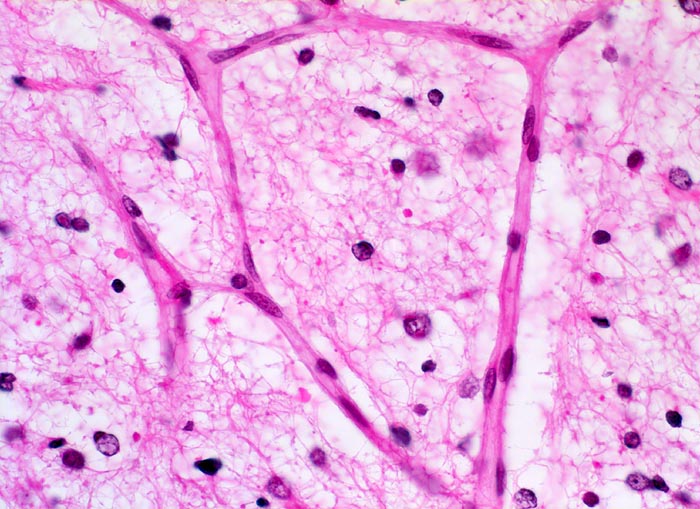

PathoPic – image database / PathoPic ID 5260 - Oligodendrogliom (WHO Grad II)

Oligodendrogliom (WHO Grad II)

maligner Tumor

Hirn frontal

Nervensystem

Das Tumorgewebe wird von einem feinen Netzwerk verzweigter Kapillaren durchzogen

Kopfschmerzen und epileptische Anfälle seit zwei Jahren.

Histologie

400